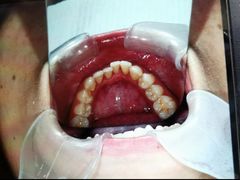

• 新达口腔(华东理工大学店)

• -新达口腔(华东理工大学店)